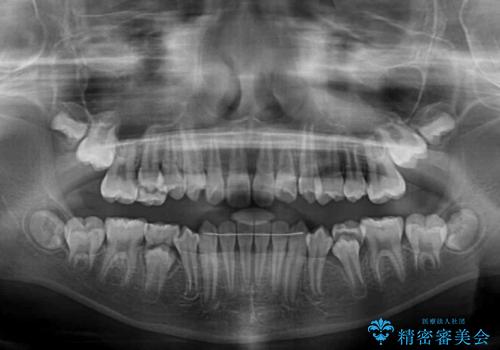

過剰歯を抜歯して前歯を排列 インビザライン・ファーストによる小学生のⅠ期治療

- 前歯の叢生を気にして来院された、小学校3年生女児の患者様です。

身長がやや低く、乳歯から永久歯への交換が少し遅い印象があったので、ワイヤー装置による1期矯正治療ではなく、乳歯も積極的に動かすことのできるインビザライン・ファーストにて治療を行うこととしました。

上顎前歯に過剰歯があったため、まずはその歯を抜歯し、傷が治癒したタイミングでインビザラインを発注することとしました。